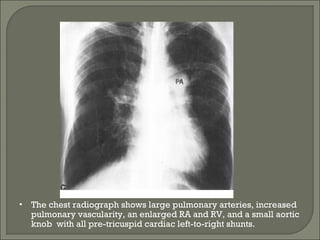

• The chest radiograph shows large pulmonary arteries, increased

knob with all pre-tricuspid cardiac left-to-right shunts.